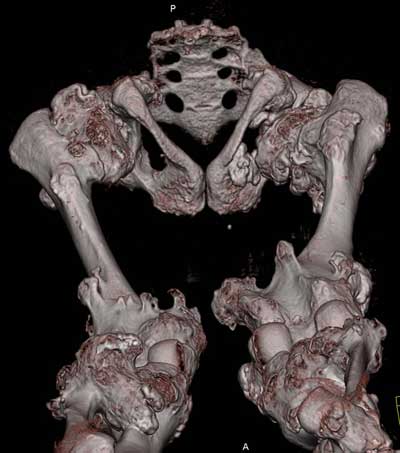

Oбратился больной 30 лет с хондродисплазией, множественными деформациями и экзостозами. Сгибательно-приводящие контрактуры Т/Б сустав, поясничный лордоз.

Интелектуально развит, работает програмистом. Болей нет. Анализы крови в пределах нормы, понижен кальций (общий Ca 1.62, N от 2.3 до 2.75;ионизорованный 0.67, N от 0.7 до 1.07) и щелочная фосфотаза -7.9. По данным КТ, оптическая плотность диафизов 150 - 200 NU (N в его возрасте 300 -350NU) метафизарный остеопороз от 100NU до отрицательных величин - 80 NU.

30 years old male with chondrodysplasia and multiple exostoses admitted.Multilevel deformities, flexion-adduction limitation of hip ROM, lumbar lordosis. Intellectually developed, working in some software company. Painless. Blood tests are normal, except low Calcium (total serum Ca 1. 62, N is 2.3 - 2.75; ionized 0.67 N is 0.7 -1.07) and low alkaline phosphatase 7.9. Diaphysis bone density is about 150 - 200 NU (N in his age is 300 - 350NU). Metaphis osteoporosis is from 100NU to minus 80 NU.

After Dr Elbatrawy saw the CT scans he added - the case has multible exostosis and the ulna also may need lengthening on both sides; he will need follow up, as one of the multible exostosis may transform to Chondrosarcoma on top of its cartilagenous cap. It is a common problem associated with this condition.